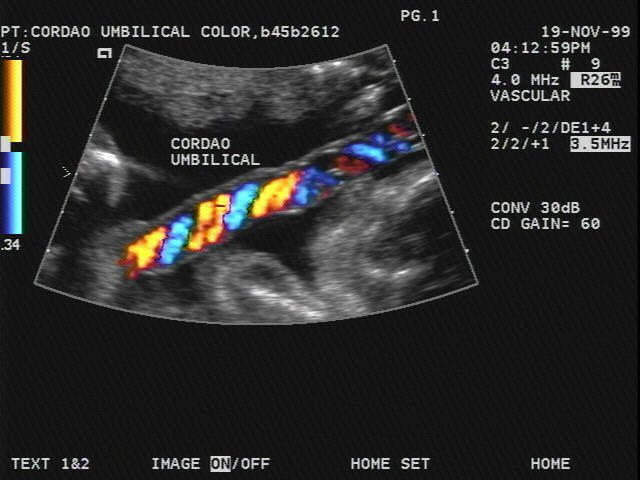

Normal 35 week pregnancy